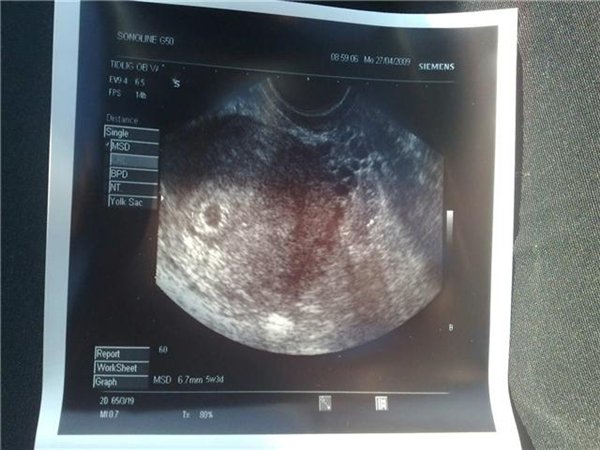

Hun scanningen + hun sagde termin ca den 24 dec.Den måler 6,7 mm....

Udfra den lille i dag skulle være 6.7 mm.

VORES BABY......6.7 mm....*SS*.

2 BILLEDE....

Vedhæftede fotos (klik for at se i fuld størrelse)